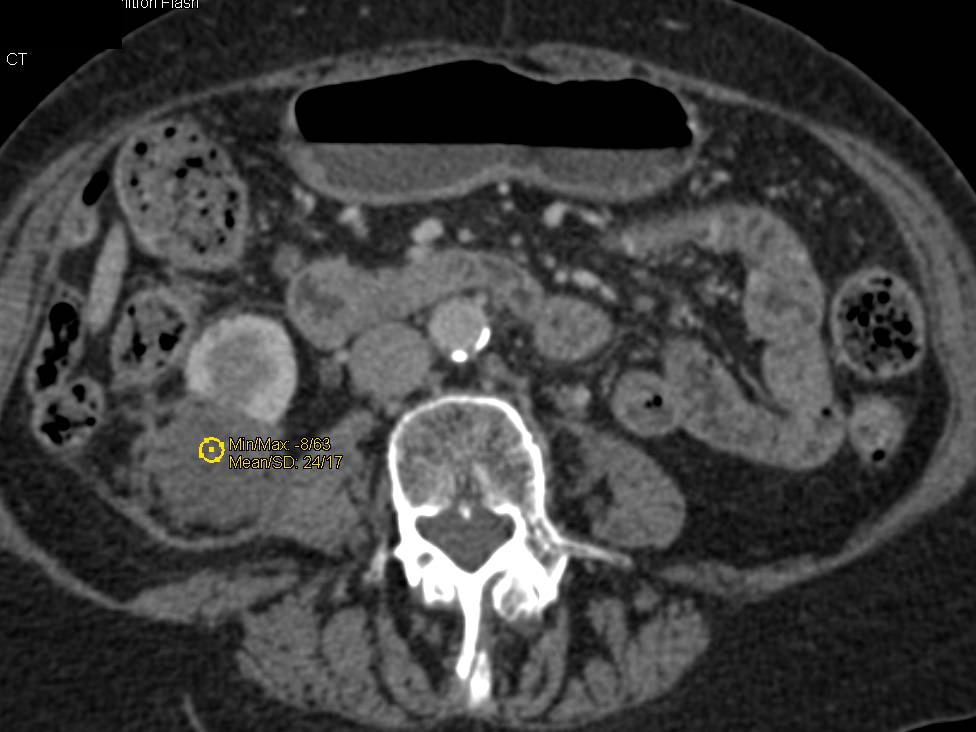

Renal Cell Carcinoma